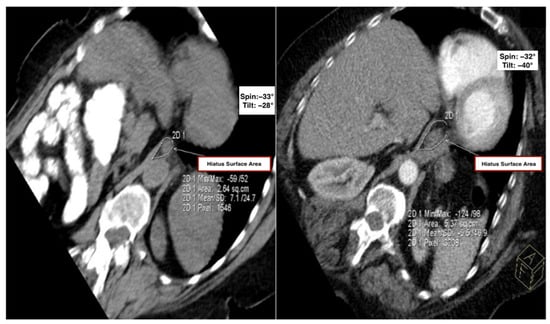

• Hiatal Surface Area (HSA): Mean HSA was significantly larger in the kyphosis group compared to controls (5.14 ± 1.31 cm2 vs. 3.59 ± 0.74 cm2; p < 0.001). A mean difference of 1.55 cm2 in HSA may appear modest, yet it represents a greater than 40% relative increase compared to controls, indicating substantial structural remodeling of the diaphragmatic hiatus that may facilitate gastric content migration and contribute to early reflux pathophysiology (Table 1 and Figure 2).

Figure 2. Comparison of the hiatal surface area between the control and kyphosis groups. Representative oblique axial MDCT images from the control group (left) and the kyphosis group (right), demonstrating measurement of hiatal surface area using a freehand region-of-interest (ROI) tool.